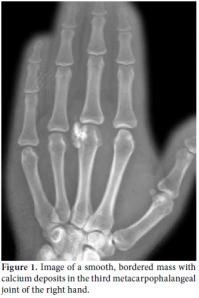

A 30-year-old female patient came to our clinic complaining of pain and swelling in the third metacarpophalangeal joint of the right hand. She described a slowly growing mass and progressively increasing pain in this joint, especially when she made a fist. A semi-rigid, fixed mass of approximately 2.5x1 cm in size was palpated in the physical examination of the patient, but there was no redness or feeling of heat emanating from it. Hand functions, such as grasping or holding, along with finger mobility were within normal limits. In addition, the patient had no other systemic symptoms or findings of arthritis such as fever, arthralgia, or swelling in the joint. A mass composed of calcium deposits was present in the third metacarpophalangeal joint of the right hand in the X-ray radiographs (Figure 1). The patient's medical history revealed nothing of consequence, and the plasma uric acid level and other routine preoperative blood tests were within normal limits, except for a slightly elevated level of the plasma pseudocholinesterase enzyme activity. While the mass lesion was dissected from the surrounding soft tissues, a milky fluid was discharged, A 2.5x1x0.5 cm size rubbery mass with a rigid center was then removed (Figure 2). Amorphous monosodium urate crystal bands surrounded by macrophages, lymphocytes, and multinuclear giant cells together with fibroblastic proliferation associated with tophaceous gout were encountered under polarized light in the histopathological examination of the removed mass (Figure 3). A detailed physical examination along with more laboratory tests and radiographs were performed after the histopathological diagnosis, and all were normal. After a one-year follow-up, the patient's plasma uric acid levels were still within the normal limits, and there had been no acute attack of arthritis. The patient was free of pain, and her hand functions were satisfactory.

There may be no findings other than soft tissue swelling surrounding the affected joint in a direct radiographic examination of acute gout arthritis.[17] Radiographic bone changes may be encountered six to eight years after the initial attack in 45% of the patients, but they are not highly specific and sensitive enough for diagnosis.[24] Magnetic resonance imaging (MRI) of tophi in soft tissues is usually nonspecific, and it may imitate neoplasia and infection. Furthermore, variable signal intensities in the T1- and T2-weighted images depend on the difference in the calcium concentration in the tophi.[10,25] Chen et al.[26] reported that calcified tophi are rare in the wrist and that the presence of such calcification probably depends on calcium crystals in conjunction with calcification in the cholesterol stored in the tophi along with an underlying calcium metabolic disorder or bone debris from large joint destruction.[27,28] In our case, there was no evidence except for smooth, bordered calcium deposits in the radiological evaluation.